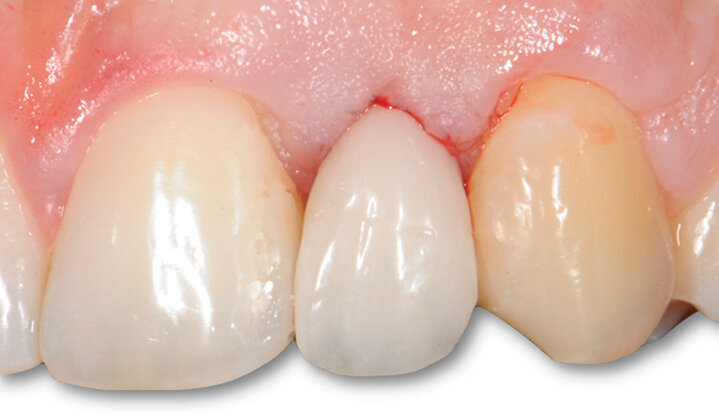

Fig. 2 - Foto inziali del caso. Si noti la presenza di elemento 12 di conformazione conoide e agenesia di elemento 22 sostituito con protesi tipo Maryland.

Una ragazza di 20 anni si è presentata alla nostra attenzione con agenesia di elemento 22 ed elemento 12 con corona di conformazione conoide. Il sito edentulo in zona 22 si presenta riabilitato con una protesi tipo Maryland (Figg. 1, 2). La paziente dal punto di vista medico generale non presentava controindicazioni al trattamento implantare. È stata valutata tramite un approccio multidisciplinare ortodontico e implantare, al fine di ottenere la migliore integrazione estetica e funzionale della riabilitazione. Dopo aver valutato le alternative terapeutiche, si è deciso per una riabilitazione di tipo protesico su supporto implantare per il sito 22 edentulo e veneer in ceramica per l’elemento 12. La paziente si presenta da noi a crescita scheletrica ultimata quindi è possibile procedere con la riabilitazione implantare. Se gli impianti venissero inseriti in fase di crescita, infatti l’osso alveolare circostante potrebbe continuare a svilupparsi verticalmente e ugualmente i denti adiacenti potrebbero continuare a erompere, creando una discrepanza poco estetica tra il margine gengivale dell’impianto, quello dei denti naturali e una infraocclusione dell’elemento dentale su impianto9.

Fig. 6c - Controllo dei tessuti molli a un mese.

Fig. 7 - Controllo dei tessuti molli a 3 mesi, non è stato ancora riabilitato il conoide.